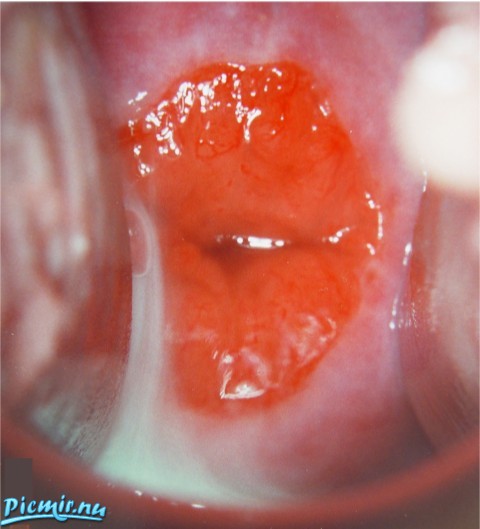

Выворот влагалища и матки

Данное видео показано к просмотру теми девушками и женщинами, которые любят в свою киску толкать чрезмерно большие игрушки.

Тёлочка страдающая выпадение влагалища решилась продемонстрировать на камеру свою патологию!

выпадение матки происходит из-за слабых мышц а не из-за предметов, умник. В меня две руки входят, но я шарик для пинпонга из письки на 4 мера выплёвываю